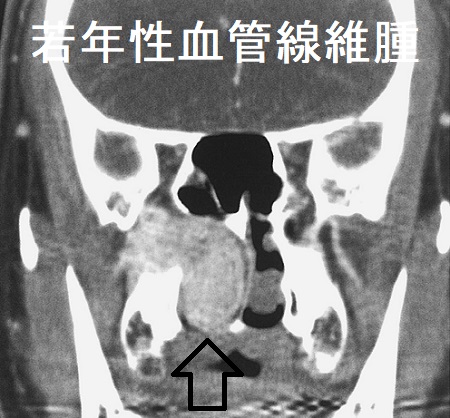

若年性血管線維腫(juvenile angiofibroma)は10-18歳の男子に多く、上咽頭に好発する極めて血管豊富な良性腫瘍で、成人すると増殖が止まります。良性腫瘍なのに、局所浸潤が強く、再発率も高いのが特徴です。

若年性血管線維腫の

- 内視鏡所見は、表面平滑で血管に富んだ腫瘍

- 副鼻腔造影CTは、造影される浸潤性腫瘤

- 確定診断は組織生検だが、大出血の危険があるため行わない事もある。所見は、小血管と線維組織。

若年性血管線維腫は出血量が多いため、良性でありながら手術による摘出が難しく、動脈塞栓後手術・ホルモン療法・放射線治療などが行われ、放射線誘発性甲状腺がんの問題があった[Laryngoscope. 1984 Dec;94(12 Pt 1):1599-605.]。